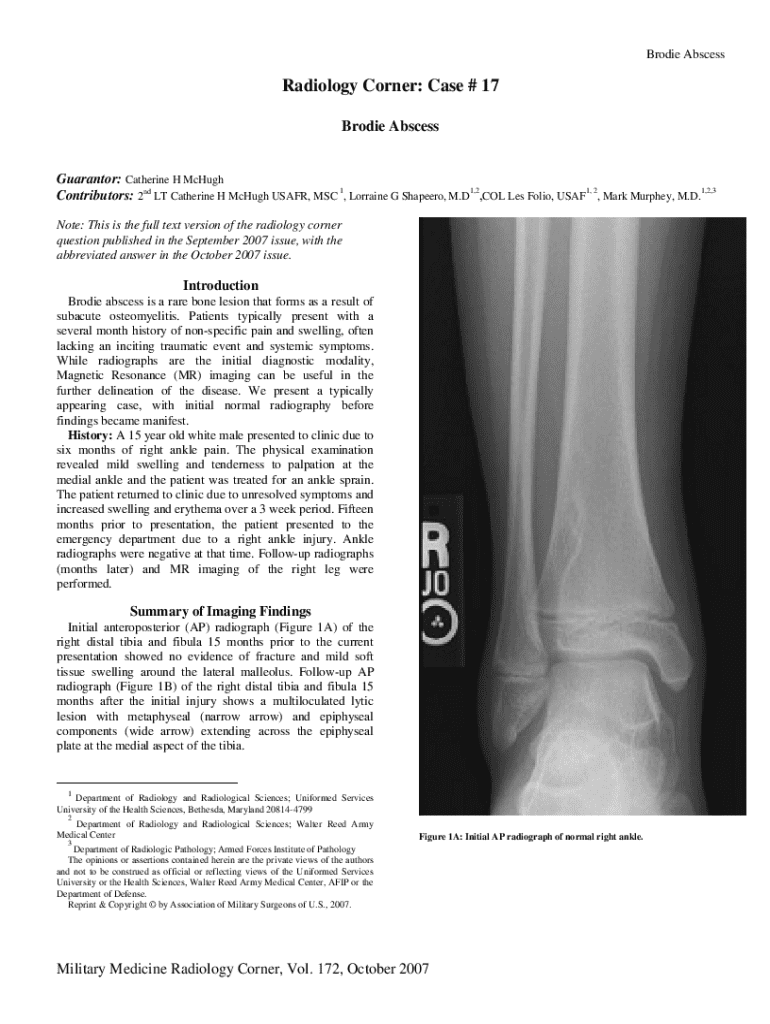

Brodie AbscessRadiology Corner: Case # 17

Brodie AbscessGuarantor: Catherine H McHugh